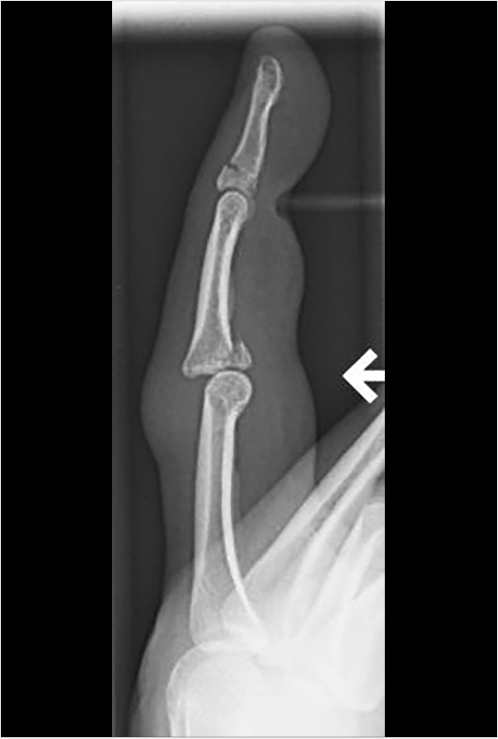

In the radiographic evaluation of hand fractures, plain radiographs are the mainstay of diagnosis. All hand injuries should be evaluated with anteroposterior (AP), lateral, and oblique radiographs. These three views are essential for visualizing the small bones in the hand to best characterize, and avoid missing, any fractures. In addition, it is best to order radiographs as specific to the injury as possible for the best view. For example, if the small finger has a deformity and a fracture is suspected, a three-view series of the small finger will yield higher quality images than a three-view series of the hand. This is because the sharpest images are obtained when the X-ray beam is centered over the area of interest; for example, hand series X-rays center the beam over the middle finger metacarpal which contrasts with dedicated finger series which center over the proximal phalanx. As a result, the AP image of a hand will capture the small finger slightly supinated potentially obscuring subtle fractures (Fig. 24‑2). In some injury patterns, additional radiograph views are useful, such as hook of the hamate view, navicular view, Robert’s view for a true AP view of the thumb, and dynamic studies such as the clenched fist view (Fig. 24‑3). 1 , 2 Computed tomography (CT) imaging is required only occasionally for fracture evaluation. Indications for CT imaging are primarily for operative planning in highly comminuted, intra-articular fractures. Magnetic resonance imaging is likewise rarely required for hand fractures, indicated mainly for detecting occult scaphoid fractures or early avascular necrosis such as in Kienbock’s disease. 2 While ultrasound imaging can be useful for soft-tissue hand injuries, it does not have utility in evaluating fractures.

When reading the radiographs, the treating physician should be able to accurately diagnose and describe the type of fracture sustained. This not only allows for determination of appropriate treatment but also ensures accurate and efficient communication with other physicians. Possible fracture patterns include transverse, oblique, spiral, and comminuted (Fig. 24‑4). Fractures are described by identifying the type of fracture, whether it is open or closed, commenting on the degree of comminution if present, the presence and direction of fracture fragment angulation, whether the fracture is apex-volar or apex-dorsal, whether there is any shortening or segmental loss of the overall bone length, measurement of any step-off of the fracture fragments, description of any rotational deformity, quantifying any articular surface involvement, and whether there is any associated joint dislocation (Fig. 24‑5).